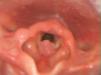

The laryngeal papillomas were detected by fibre-optic laryngoscopy, and an excision was performed (Fig. 1) by endolaryngeal microsurgery. In 4 of the 6 cases they received intraoperative adjuvant treatment with intralesional cidofovir on at least one occasion. Case 2 also received oral propranolol daily for a year. The histological findings were consistent with papillomatosis, and serotype HPV-11 was identified in cases 2 and 3 and HPV-6 in case 6.